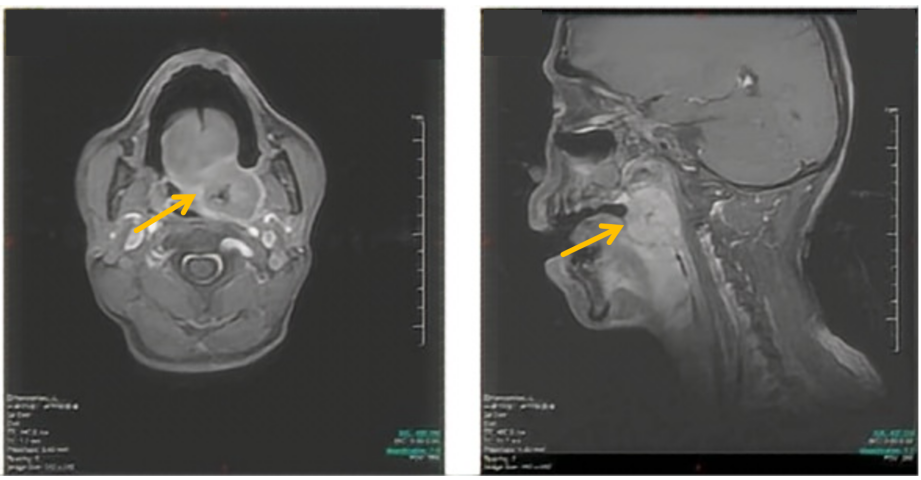

自2025-1-22起,予戈利昔替尼150mg qd联合PD-1单抗200mg ivgtt q3w方案治疗6个周期,疗效评估达CR。治疗期间患者出现Ⅱ度白细胞减少,予粒细胞集落刺激因子

2025-8-26随访,患者仍维持CR。

截至目前,患者继续戈利昔替尼+PD-1单抗治疗中

图2 戈利昔替尼联合PD-1单抗治疗前后患者影像学表现